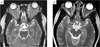

Background: Existing therapies for recurrent or refractory histiocytoses, including Langerhans cell histiocytosis (LCH), juvenile xanthogranuloma (JXG), and Rosai-Dorfman disease (RDD), have limited effectiveness. We report our experience with using clofarabine as therapy in children with recurrent or refractory histiocytic disorders, including LCH (11 patients), systemic JXG (4 patients), and RDD (3 patients).

Results: Patients were treated with a median of three chemotherapeutic regimens prior to clofarabine. Clofarabine was typically administered at 25 mg/m(2) /day for 5 days. Cycles were administered every 28 days for a median of six cycles (range: 2-8 cycles). Seventeen of 18 patients are alive. All surviving patients showed demonstrable improvement after two to four cycles of therapy, with 11 (61%) complete responses, 4 (22%) partial responses, and 2 patients still receiving therapy. Five patients experienced disease recurrence, but three of these subsequently achieved complete remission. All patients with JXG and RDD had complete or partial response at conclusion of therapy. Side effects included neutropenia in all patients. Recurring but sporadic toxicities included prolonged neutropenia, severe vomiting, and bacterial infections.

Conclusion: Clofarabine has activity against LCH, JXG, and RDD in heavily pretreated patients, but prospective multi-center trials are warranted to determine long-term efficacy, optimal dosing, and late toxicity of clofarabine in this population.